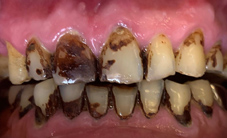

噴砂美白前

噴砂美白後